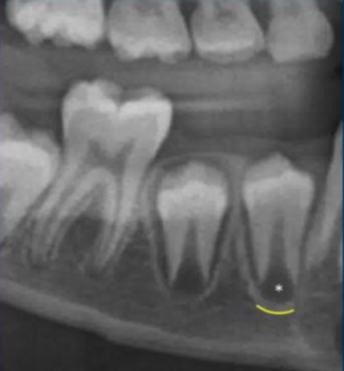

what is this superimposition?

mental foramen